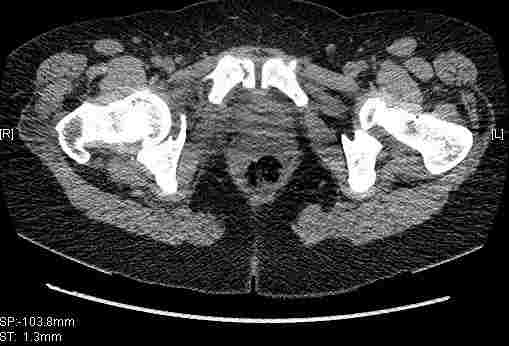

Re: Т-образный перелом вертлужной впадины

Удалось сегодня вывести пациентку в соседнюю больницу, где есть кт. Срезы сделаны только горизонтальные.